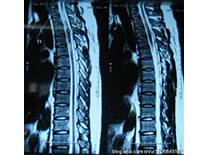

脊柱棘突痛是脊柱上的韧带损伤,主要由于反复应力作用或急性损伤未能治愈所引起。常见于体操、跳水、排球运动员和体育爱好者以及肩负重者。健康处方1.运动时减少腰背的过伸或弯腰作业。2.宽腰带保护,防止再伤。3.加强腰背肌力练习。4.服消炎镇痛药物或痛点封闭等治疗。5.无效时,可做小针刀治疗、针灸治疗。